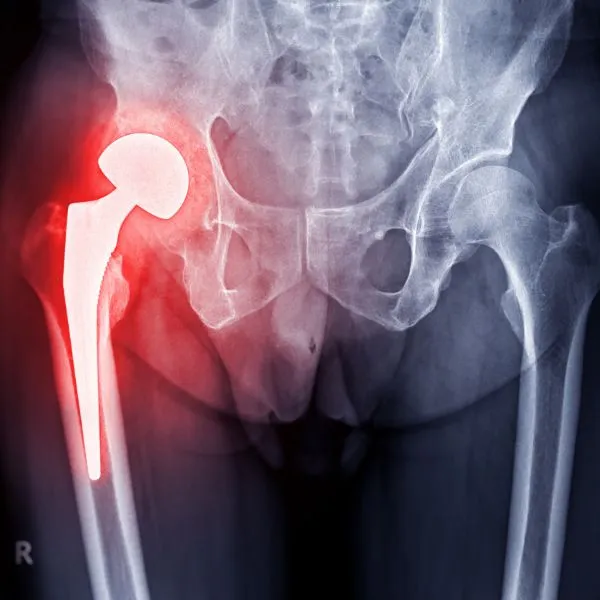

Total Hip Replacement

Hip Arthroplasty